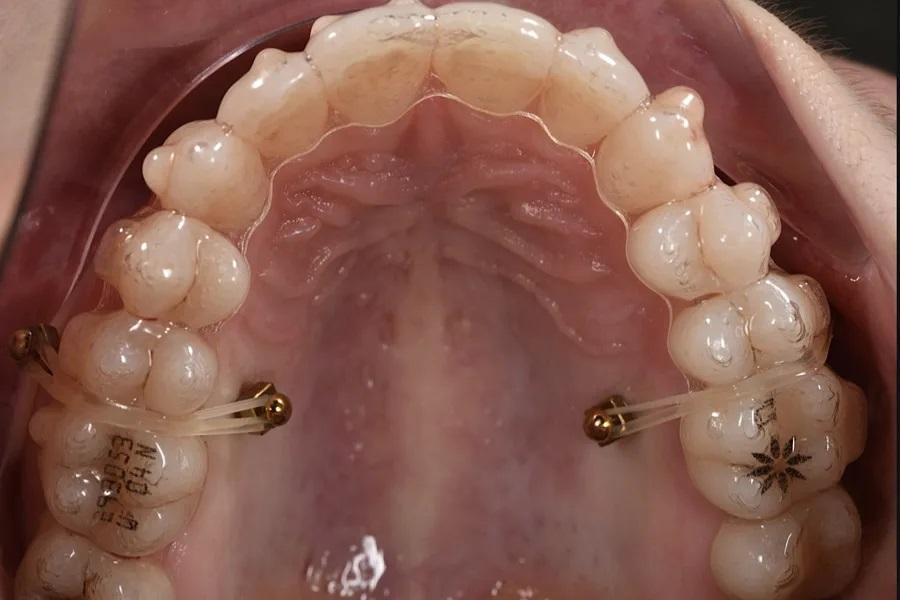

Интрузия боковых зубов (например, примерно на 2–3 мм в области моляров) моделируется для определения авторотации нижней челюсти пр. ч. с. с обеспечением адекватного переднего ведения и функционального пространства движений. Использование гибридных (аналогово-цифровых) или полностью цифровых методов отслеживания движений нижней челюсти/аксиографии повышает точность определения конечного положения нижней челюсти по завершении лечения (фото 9 – 12).

Фото 10. Окклюзионный вид интрузии с опорой на ВОУ при использовании элайнеров и эластиков; показаны расположение, биомеханика и используемые аппараты.